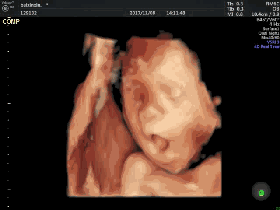

懷孕第26週 4d超音波 屬於臭妹的日誌 隨意窩xuite日誌

怀孕26周 怀孕第26周胎儿图 怀孕26周四维彩超图 怀孕26周胎动 注意事项 好运宝贝

懷孕26周做四維彩超 看到彩超里的寶寶 瞬間被醫生臭罵一頓 每日頭條